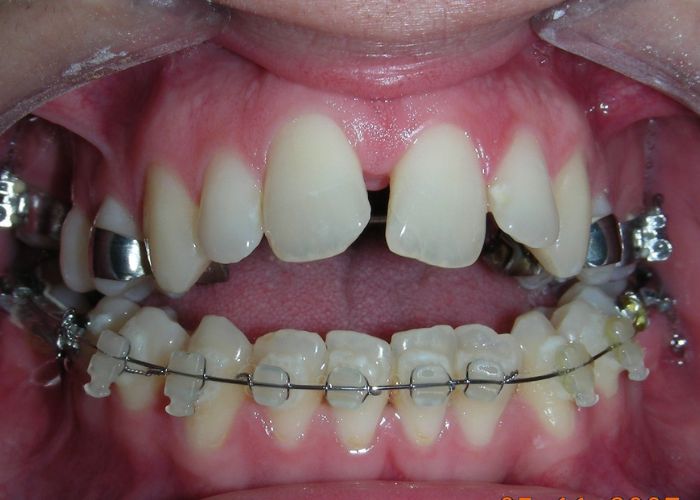

The patient presented with an anterior open bite, characterized by the absence of vertical overlap between the upper and lower incisors, and bilateral posterior crossbite. Extraoral examination revealed a vertically long facial pattern with an increased lower third of the face. The profile is convex with a retruded chin, indicating sagittal and vertical skeletal imbalances. We find also the inclined bipupillary line, which corresponds to facial asymmetries and altered occlusal plane.

Intraoral Examination:

Absent #16, #36 and #46 , No Angle molar relationship . Projection of canines axes in class II relationship . Anterior open bite: Over Bite – 8 mm). Bilateral posterior crossbite: Involvement of upper posterior sectors with inverted buccal-lingual relationship. Moderate Crowding at the level of the upper and lower incisors. Acceptable Oral Hygiene with no periodontal issues

Extraoral clinical examination revealed a vertically long face with an increased lower facial third. The facial profile was slightly convex, with poor chin projection. Intraoral examination showed an AOB and bilateral posterior crossbite.